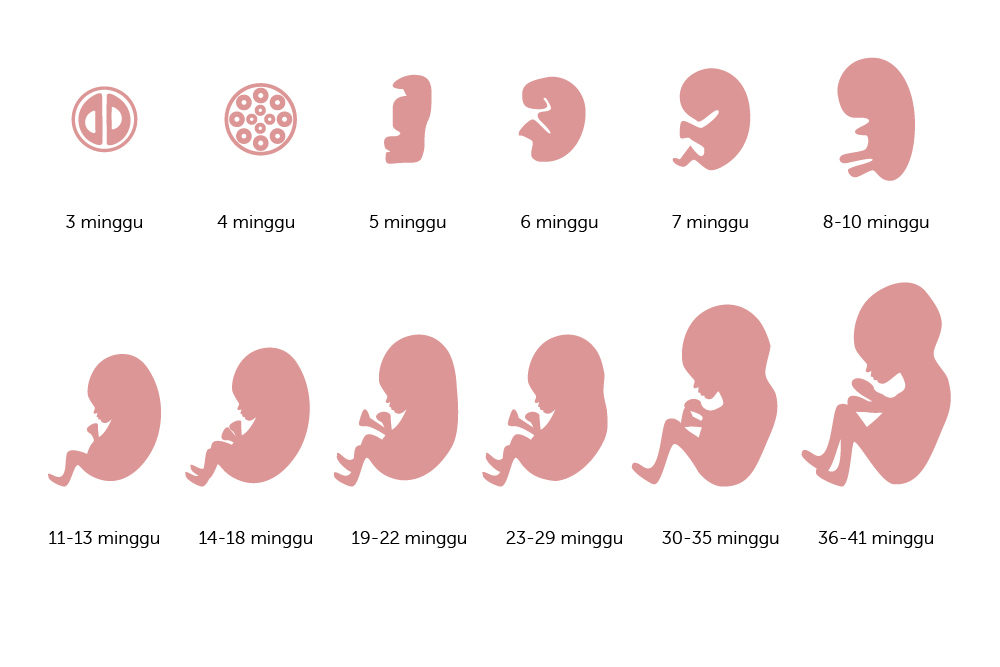

Perkembangan Janin Minggu ke Minggu 1-40 : Gambar Lengkap

Perkembangan Janin Minggu ke Minggu 1-40 : Gambar Lengkap

Tahapan masa kehamilan

Tahapan masa kehamilan